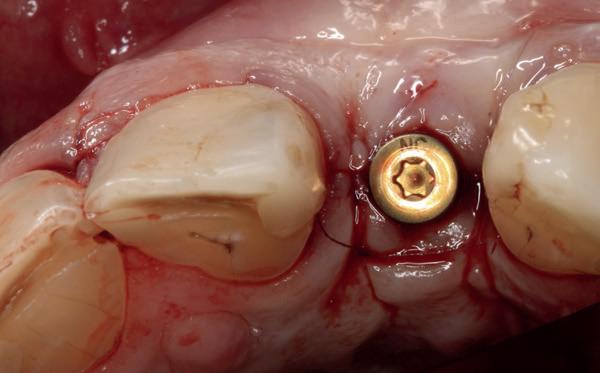

van de patiënt, om eerst weer vaste apparatuur terug te plaatsen om de radices in een divergerende stand te plaatsen. Gelukkig verliep deze behandeling voorspoedig. (afbeelding 2 -4). Het volgende behandelplan werd gemaakt:

• Intra-orale scan voor studiemodellen, proefopstelling en beoordelen ruimte palatinaal

Vervaardigen essix retainer met dummies waarbij er een emergence profile van de 11 en 21 werd gevormd door eivormige dummies 4 mm in de gingiva te plaatsen

• Aanvulling zachte weefsels met de VISTA techniek en een vrij gingivatransplantaat uit het palatum links en direct dragen van de essix retainer

Na 4 weken intra-orale scan voor de etsbrug en kleurbepaling bij de technicus

• Plaatsen van de etsbrug met een composietcement

Voordat er gescand kon worden voor een etsbrug, werd een studiemodel vervaardigd om met de technicus te overleggen of er voldoende ruimte was voor 2 centrale incisieven in de mesio-distale zin en of er voldoende ruimte was in occlusie voor de vleugels van de etsbrug. Er hoeft enkel nog aan de 12 en 22 pala-

tinaal geslepen te worden als er geen 1,5 mm ruimte voor de vleugels behaald kan worden. De ruimte was op de dunste plekken 1 mm, dus een kleine preparatie in de 12 en 22 palatinaal was nodig. Omdat de kaak volledig afgevlakt was en dun was geworden, kunnen de dummies van de etsbrug enkel op de kaak “gelegd worden”, maar daarbij zijn er geen papillen en staat de cervicale rand van de dummies net voor de kaak. Een esthetisch resultaat kan daarmee niet behaald worden. Daarom is een aanvulling van de zachte weefsels in de breedte nodig, als het creëren van een emergence profile, waarbij het oogst alsof de gebitselementen uit het weefsel vertrekken.

14. Direct postoperatief plaatsen

van de essix met 2 dummy tanden

15. Twee weken post operatief

16. Creëren van een duidelijke indeuking in de mucosa voor emergence profile

17. Genezing van het palatum

18. Etsbrug frontbeeld

19. Etsbrug palatinaal